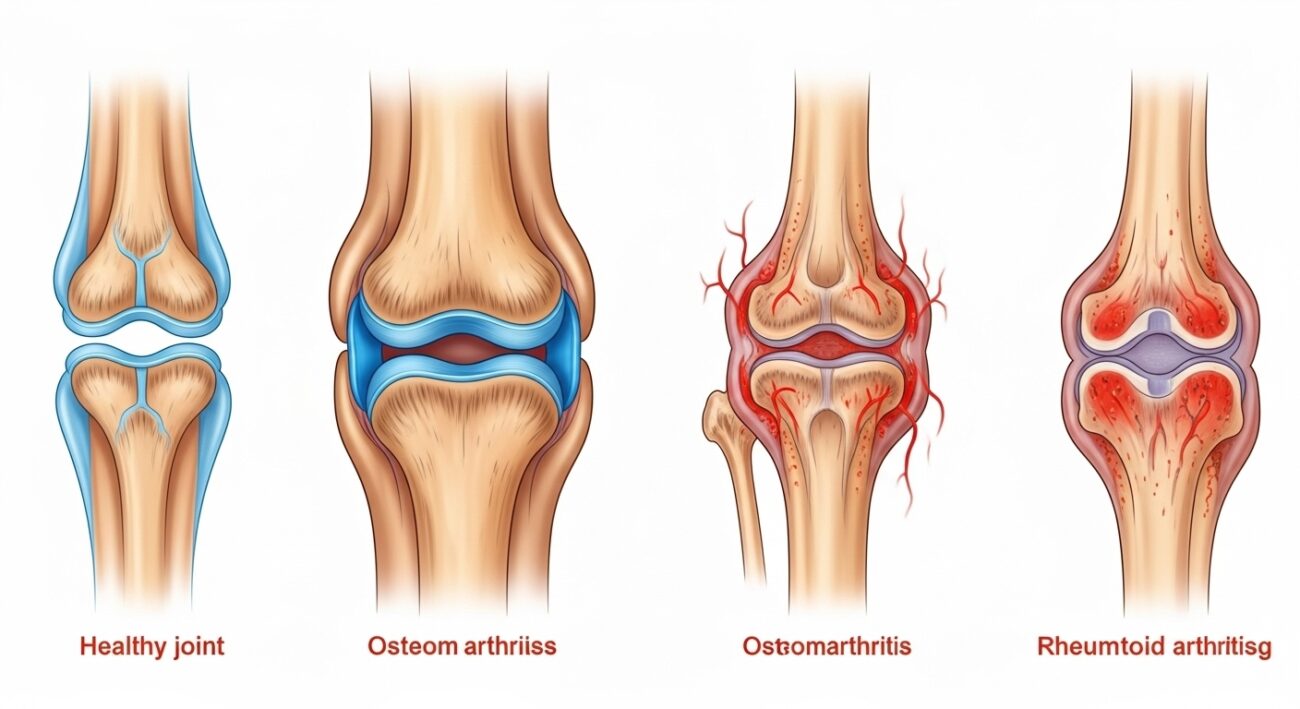

4. Attrition in Healthcare

In healthcare, attrition can be used to describe the gradual decline of a patient’s health due to chronic diseases or aging. This slow deterioration can make it harder for healthcare providers to manage patients effectively. Understanding the process of health attrition allows for better care and preventive measures, such as regular checkups and lifestyle changes.